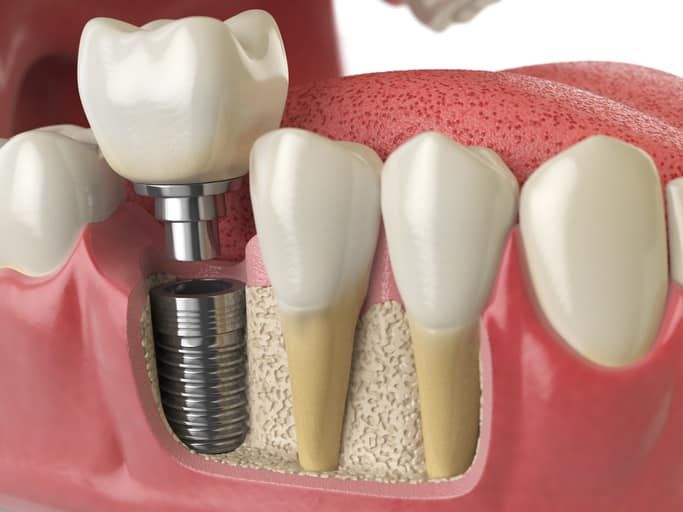

Răng implant, giải pháp khôi phục răng mất bằng cách cấy ghép trụ implant vào xương hàm. Với hình dạng giống chân răng thật, trụ implant được làm từ titanium, vật liệu sinh học cao cấp. Tích hợp với xương hàm, bác sĩ sẽ gắn mão răng sứ để khôi phục chức năng ăn nhai và vẻ đẹp tự tin. Nha Khoa Tâm An tự hào là địa chỉ uy tín trồng răng implant tại Phú Yên. Nơi đây sở hữu trang thiết bị hiện đại và đội ngũ bác sĩ giàu kinh nghiệm.

- Chụp phim X-quang: Kiểm tra xương hàm, xác định vị trí cấy ghép trụ implant.

- Cấy ghép trụ implant: Bác sĩ sử dụng dụng cụ chuyên dụng cấy ghép trụ implant vào xương hàm.

- Phục hình răng sứ: Sau khi trụ implant tích hợp với xương hàm, gắn mão răng sứ để khôi phục chức năng và vẻ đẹp răng.